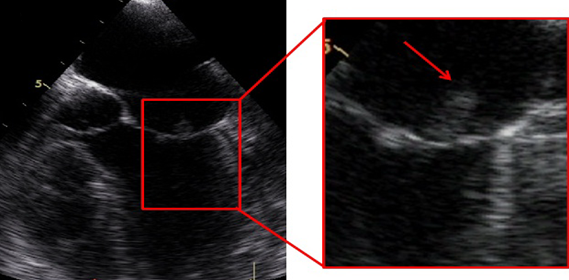

On the second day of her hospitalization, she had melena and gastroenterology adviced proton pump inhibitor. Her hemoglobin was 7.1 g/dL and 2 units of erythrocyte suspension were given. The patient had diffuse myalgia, palpitations and sinus tachycardia on electrocardiography. Her heart sounds were regular without murmur. During a physical examination, painless hemorrhagic cutaneous lesions were noted on her feet (Figure 1 [Fig. 1]). She was directed to cardiology and on echocardiography mild mitral regurgitation was noted. Transesophageal echocardiography (TEE) was planned in order to detect mitral regurgitation etiology. TEE showed mild mitral regurgitation and a vegetation on posterior mitral valve (Figure 2 [Fig. 2]). She was diagnosed with infective endocarditis and therapy was changed. Gentamicin (2x80 mg) plus ampicillin (4x3 gr) was started. On follow-up the patient still had fever, myalgia and discomfort. Two blood cultures revealed gram positive bacteria resistant to methicillin and the bacteria was identified as Staphylococcus aureus with BD Phoenix Automated Microbiology System. Also fluid sample (the fluid sample taken from her ankle) culture done in sheep blood agar revealed gram positive bacteria resistant to methicillin and the bacteria was identified as Staphylococcus aureus with BD Phoenix Automated Microbiology System. Both of the cultures’ isolates were resistant to methicillin and sefoxitine and susceptible to vancomycin, linezolid and teicoplanin. Although gentamicin plus vancomycin therapy was planned for the patient, vancomycin was not available so her therapy was changed to gentamicin (2x80 mg) plus linezolid (2x600 mg) according to culture antibiogram. The patient began to improve after medical therapy with linezolid and gentamicin. She had no fever anymore and her hemoglobin level was 9 g/dL. Blood urea and creatinine were in normal ranges 30 and 1 g/dL, respectively. In the third day her CRP-level began to decrease (20.1 mg/dL). Her CRP course was 12.6 mg/dL in the first week, 5.8 mg/dL in the second week, 3.2 mg/dL in the fourth week and 0.5 mg/dL in the sixth week. Control TEE showed mild to moderate mitral regurgitation and vegetation (Figure 3 [Fig. 3], Figure 4 [Fig. 4]). After six weeks of antibiotherapy (six week linezolid and two week gentamicin) she was free of infection and a control transthoracic echocardiography showed no mitral regurgitation or vegetation.

Figure 3: Vegetation on posterior mitral valve (control)

Figure 4: Mild to moderate mitral regurgitation